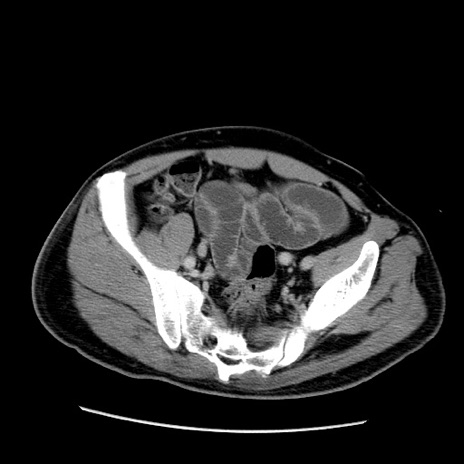

冠状断像

【症例】50歳代男性

【主訴】腹痛

【現病歴】AVMからの被殻出血のため回復期リハ病棟入院中。 本日午後3時頃急に下腹部痛が出現した。

【既往歴】AVM、被殻出血、虫垂炎、高血圧

【身体所見】意識晴明、左半身不全麻痺、会話の理解は良好、36.5°C、腹部:膨隆、全体に板状硬、下腹部正中に圧痛点あり、反跳痛-、筋性防御不明、右下腹部にope scar

【データ】WBC 9400、CRP 0.06